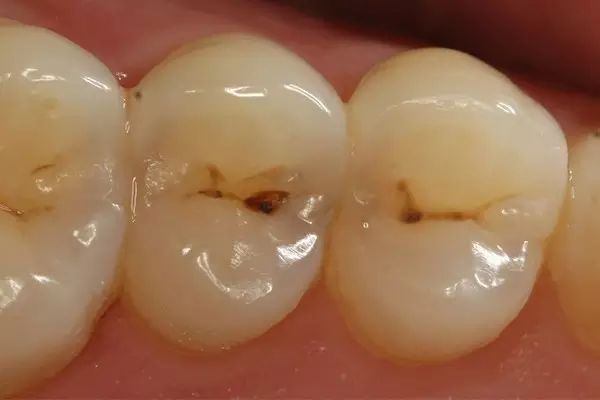

第三步:深龋

当您进食时,没法咬食物,您说:“还好,可以用另外一边牙齿咬。”

牙医告诫说:“病变已经破坏到了牙本质深层,牙齿有较深的龋洞,温度刺激,化学刺激以及食物进入龋洞时均引起疼痛,此时,及时做充填治疗的话还来得及保住牙髓。”